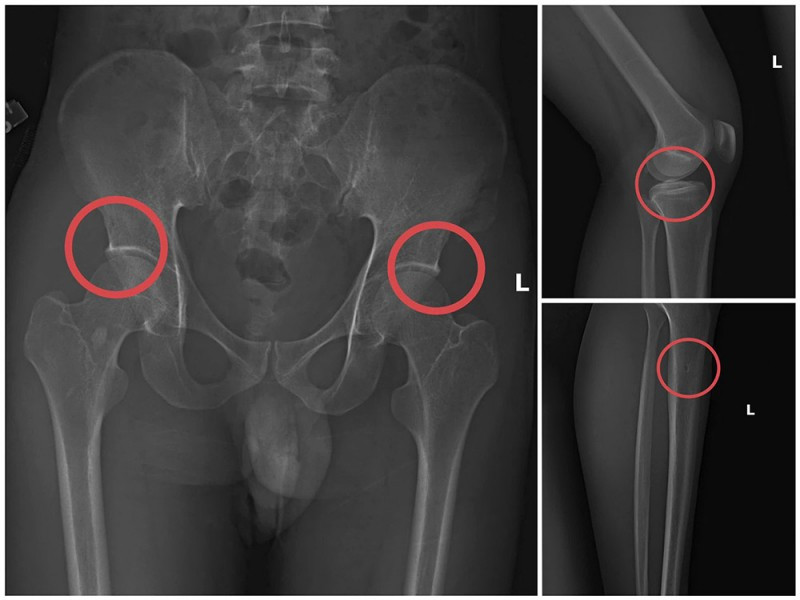

Phim chụp XQ một số tổn thương xương do đối tượng Tạ Minh Châu tạo ra.

Tại đây, Châu tiêm thuốc mê vào tĩnh mạch tay phải của người mua bảo hiểm. Khoảng 1 phút sau khi đối tượng mê đi, Châu dùng búa và kim tiêm đục, đâm vào vị trí đã thống nhất để tạo tổn thương xương (thường là làm rạn nứt hoặc vỡ xương chậu, xương đùi…).